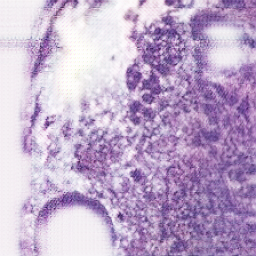

The Figure 4 illustrates how CycleGAN outputs evolve across training epochs. Each column shows the virtual H&E image generated at a specific epoch, while each row corresponds to the same slices. Early in training, the images may exhibit incomplete or uneven staining and less clear tissue structure.

As training progresses, the representation of H&E changes slightly and becomes visually more consistent. However, through comparison across epochs, it can also be observed that the CycleGAN generated results exhibit certain drawbacks, including variability in staining intensity, occasional loss of fine structural details, and the introduction of artificial texture patterns that are not present in the original fluorescence images. Due to the lack of ground truth H&E images, the quality of the generated virtual H&E cannot be quantitatively validated in this study and is assessed primarily through visual inspection. If paired ground truth H&E data were available, quantitative performance metrics such as cell count agreement or dice score and intersection of union (IOU) of the stained cells (positive cells) in the virtually generated image with respect to the real image [2].

| Epoch 20 | Epoch 60 | Epoch 100 |